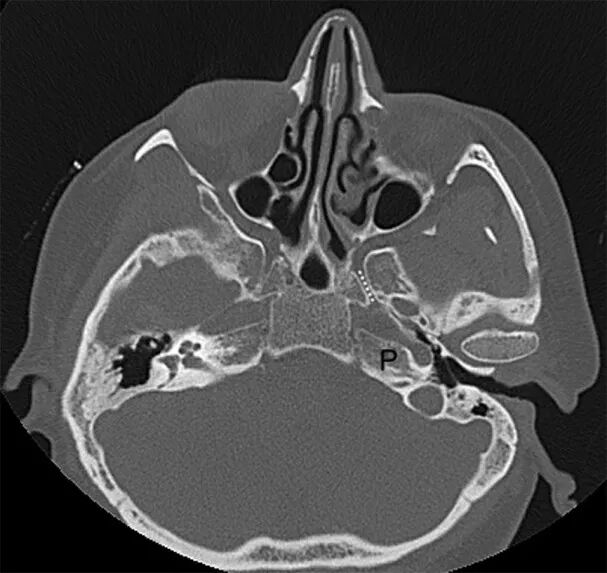

图3. CT轴位图像显示翼管走行(虚线),其开口于pICA水平。在内镜下扩大经鼻翼突入路时,可将pICA向外侧推开,以到达岩尖的病变。